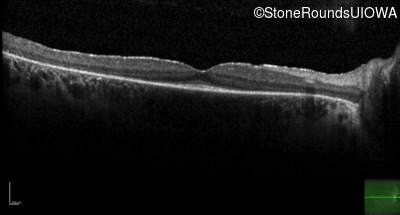

Optical Coherence Tomography - Left -

20/20

Exemplar / OCT Stack